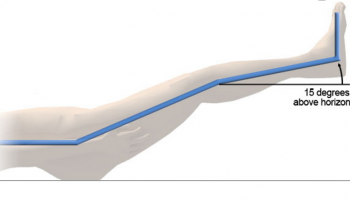

این زخم ها ممکن است بدون درد باشد اما درد در صورت وجود ممکن است با بالا گذاشتن پا بهتر شود.

بالا نگه داشتن پا